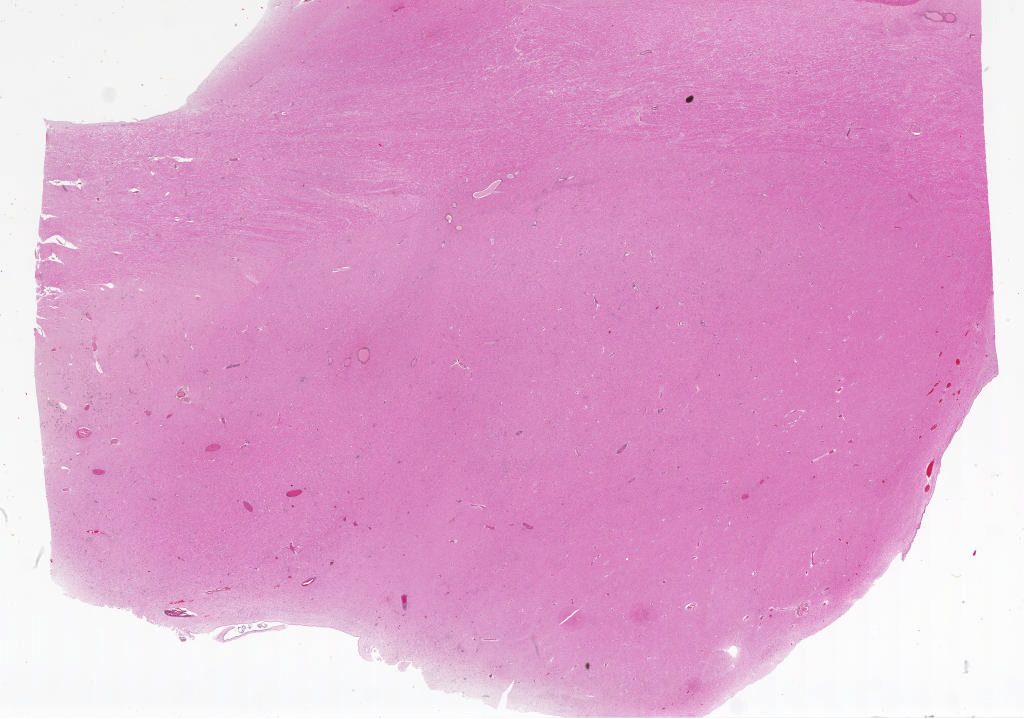

KulichCase3.svs

66000

x

46295

20X